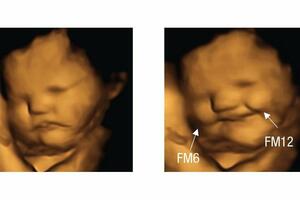

Nerođene bebe se „smješkaju” šargarepi i „mršte” kelju, pokazalo...